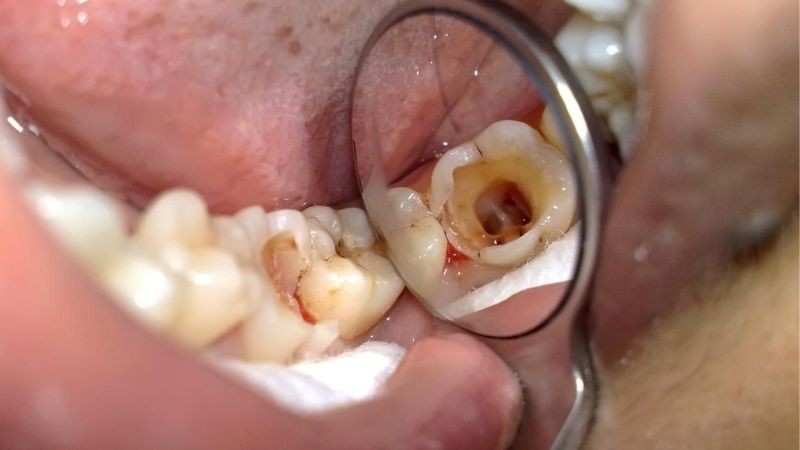

Sâu răng

Sâu răng là nguyên nhân gây ra tình trạng đau răng hàm dưới bên trái thường gặp nhất. Sâu răng chủ yếu do vệ sinh răng miệng không tốt, các mảng bám tích tụ trên bề mặt răng được vi khuẩn lên men tạo thành axit ăn mòn lớp men răng, ngà răng, nặng hơn có thể lan vào đến tủy răng.

Dấu hiệu nhận biết tình trạng răng sâu là bề mặt răng có màu vàng đục, khi nặng hơn là xuất hiện những chấm đen li ti, răng bị đau nhức, ê buốt dữ dội. Các cơn đau răng sẽ xuất hiện thường xuyên hơn khi ăn những thực phẩm chua, cay, ngọt hay quá nóng, quá lạnh.

Sâu răng là nguyên nhân phổ biến dẫn đến đau răng hàm dưới bên trái